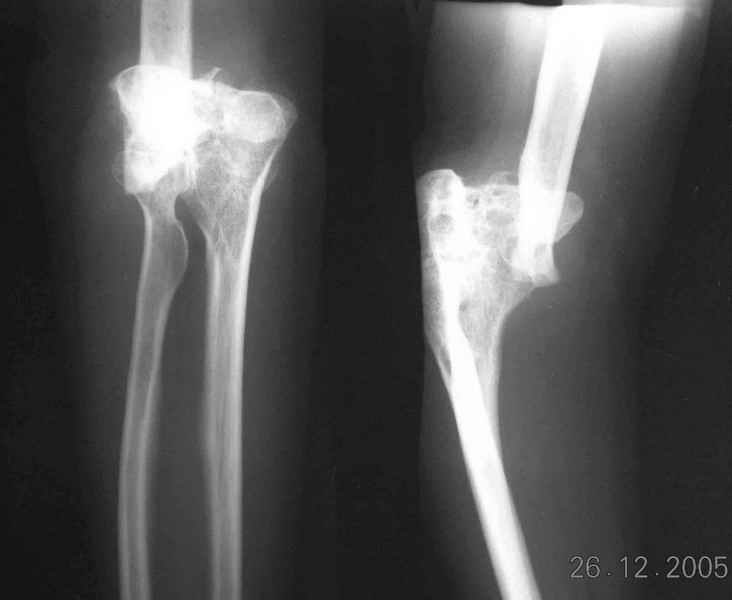

The recent x rays show established Non union with poor quality bone in the distal fragement. The joint is also appearing degenerate. In view of the multiple failed reconstructive surgeries, an Elbow replacement would seem reasonable.

Obviously there is no elbow joint...the options are few: (from the worst to the "best"...if any)

1. Arthrodesis - last choice if at all

2. If no pain leave it as it is